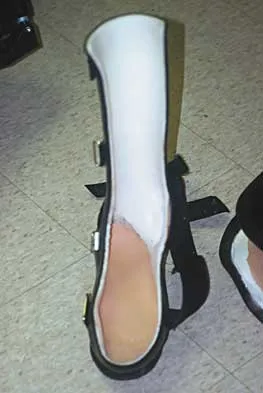

The orthosis shown in Figure 47 is commonly used for

Explanation